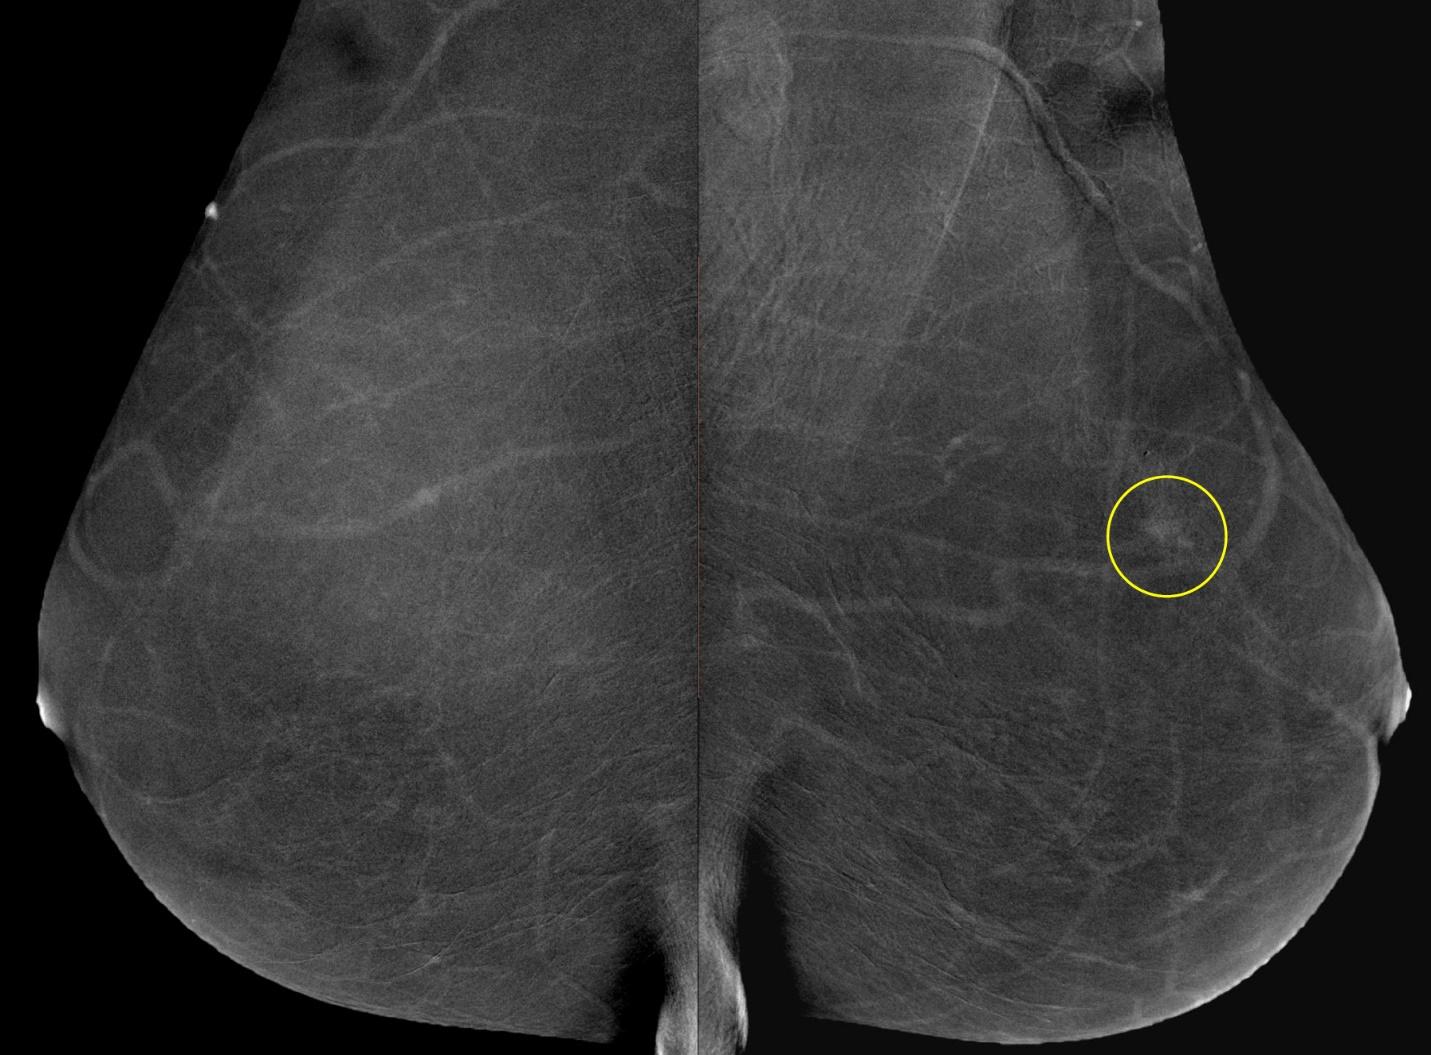

Метод прицельной маммографии с увеличением применяется для более детального исследования определенной области молочной железы. Он отличается высокой точностью диагностики. В отличие от обычной маммографии, которая предоставляет более общую информацию о состоянии молочных желез, прицельная маммография с увеличением позволяет получить точные данные о процессах, происходящих в тканях, благодаря методу компрессии конкретного участка.